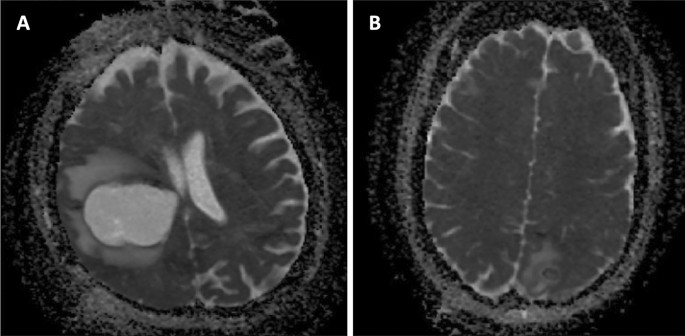

A single representative slice of the ADC map showing the REL in the longest diameter as well as containing the characteristic perilesional edema was chosen by a skilled clinician for every patient on the diagnostic MRI and loaded into the program to perform the analysis (Fig. 2). For this purpose, five linear lines of interest (LOI) were placed into a single representative slice of the ADC map. The LOI function was programmed in Matlab to approximate the ADC values between the selected points linearly. The ADC values were then saved as a vector.

The analysis of the data defined by the LOI was carried out in order to select the predictors for the machine learning algorithms. Figure 3b shows the waveform of the values represented by the red LOI (Fig. 3a). Based on the data analysis, the following predictors were chosen (from left to right): the gradient of the leading edge of the onset of the perilesional brain edema (gradient 1), \(\nabla ADC_{{{\text{E}}_{rise} }}\); the median ADC values (plateau 1), \(\overline{{ADC_{{\text{E}}} }}\); the standard deviation of the ADC values, \(\sigma_{{ADC_{{\text{E}}} }}\)(plateau 1); the transition between the perilesional brain edema and the enhancing ring (gradient 2), \(\nabla ADC_{{{\text{E}}_{fall} }}\); the transition between the enhancing ring and the REL core (gradient 3), \(\nabla ADC_{{{\text{T}}_{rise} }}\); the median ADC values (plateau 2), \(\overline{{ADC_{{\text{T}}} }}\); the standard deviation of the ADC values, \(\sigma_{{ADC_{{\text{T}}} }}\) (plateau 2). To discriminate between the glioblastoma and abscess, a set of boxplots was created.